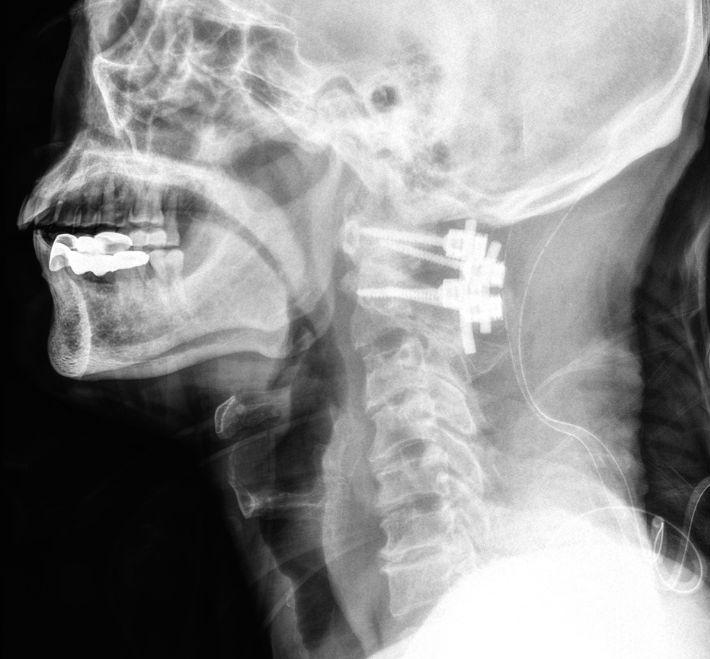

The Complete Guide to Minimally Invasive Cervical Spine Surgery: How "Navigated Minimally Invasive" Techniques Precisely Relieve Nerve Compression and Speed Recovery

Numb hands, weakness, unsteady gait—when cervical nerves are compressed, your quality of life suffers. Do you feel anxious upon hearing that cervical spine surgery might be needed, fearing the large incision, long rehabilitation, and complications of traditional surgery?

Today, cervical spine surgery has entered the era of "precision minimally invasive" techniques. The Dr. Chien-Chun Chang Minimally Invasive Spine & Joint Team, with the assistance of "3D computer navigation" and "high-end endoscopy", can select the least traumatic approach based on your specific type and location of compression to achieve the goal of effective decompression and rapid recovery.